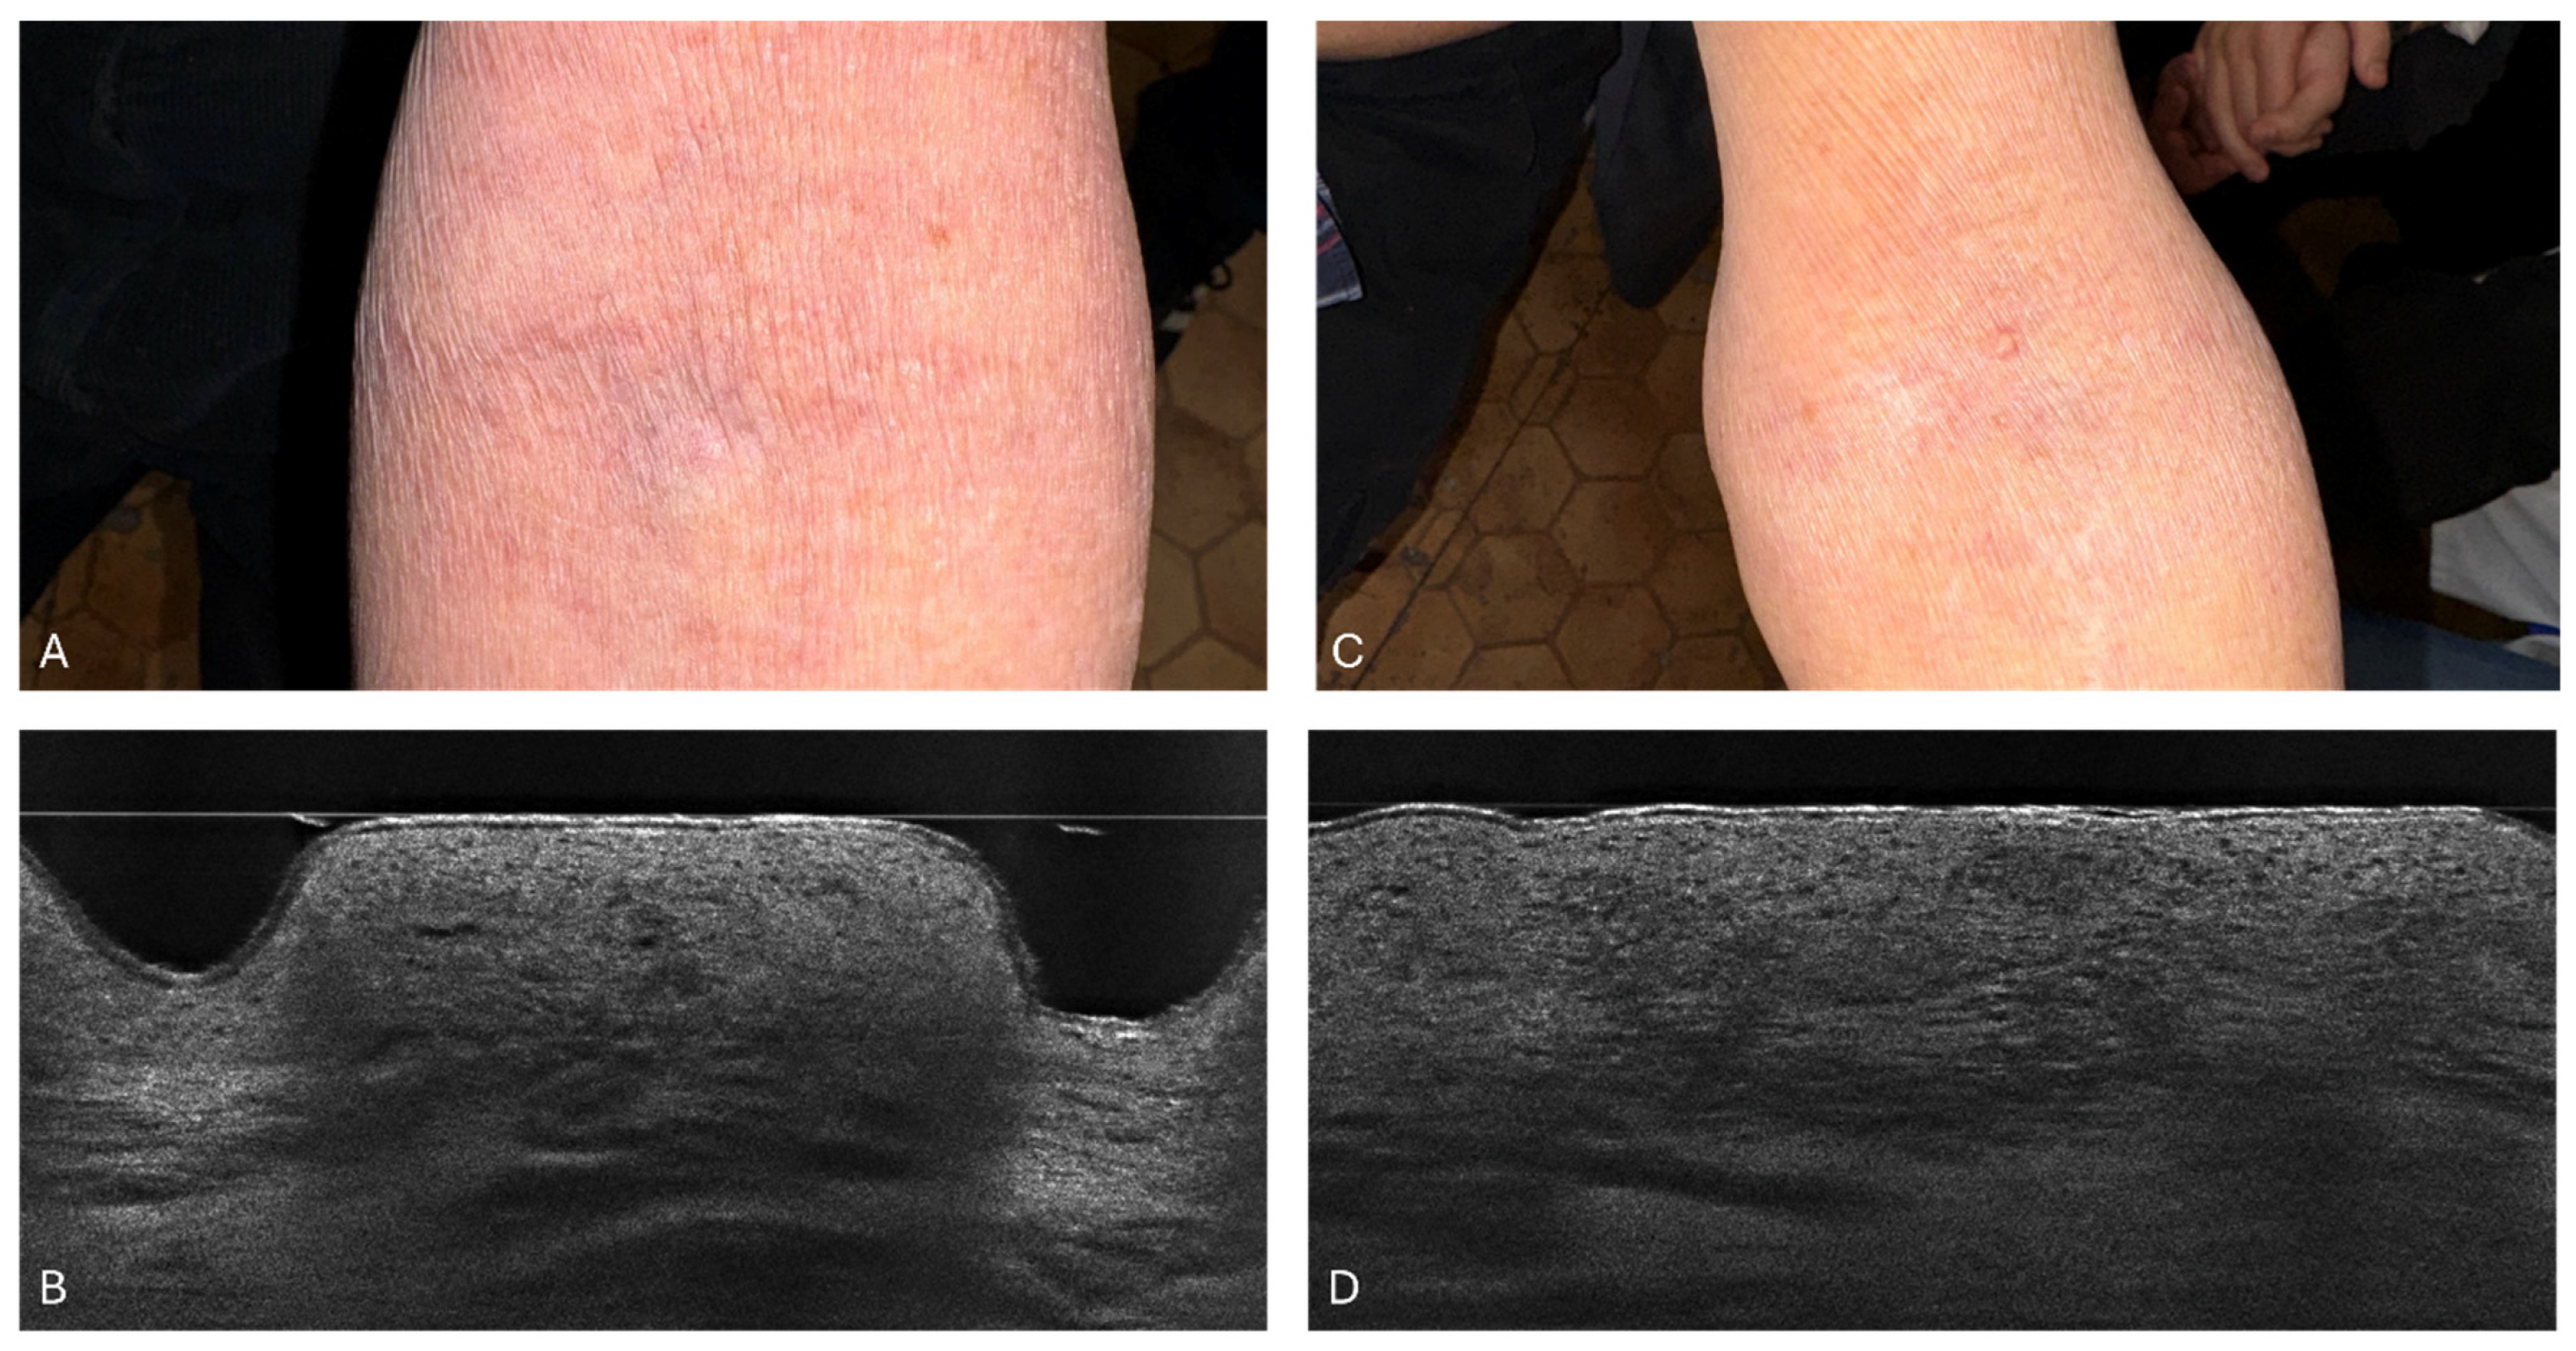

3.1. Atopic Dermatitis in LC-OCT

3.2. Stratum Corneum Thickness

3.3. Stratum Corneum Disturbances

3.4. The Epidermal Thickness